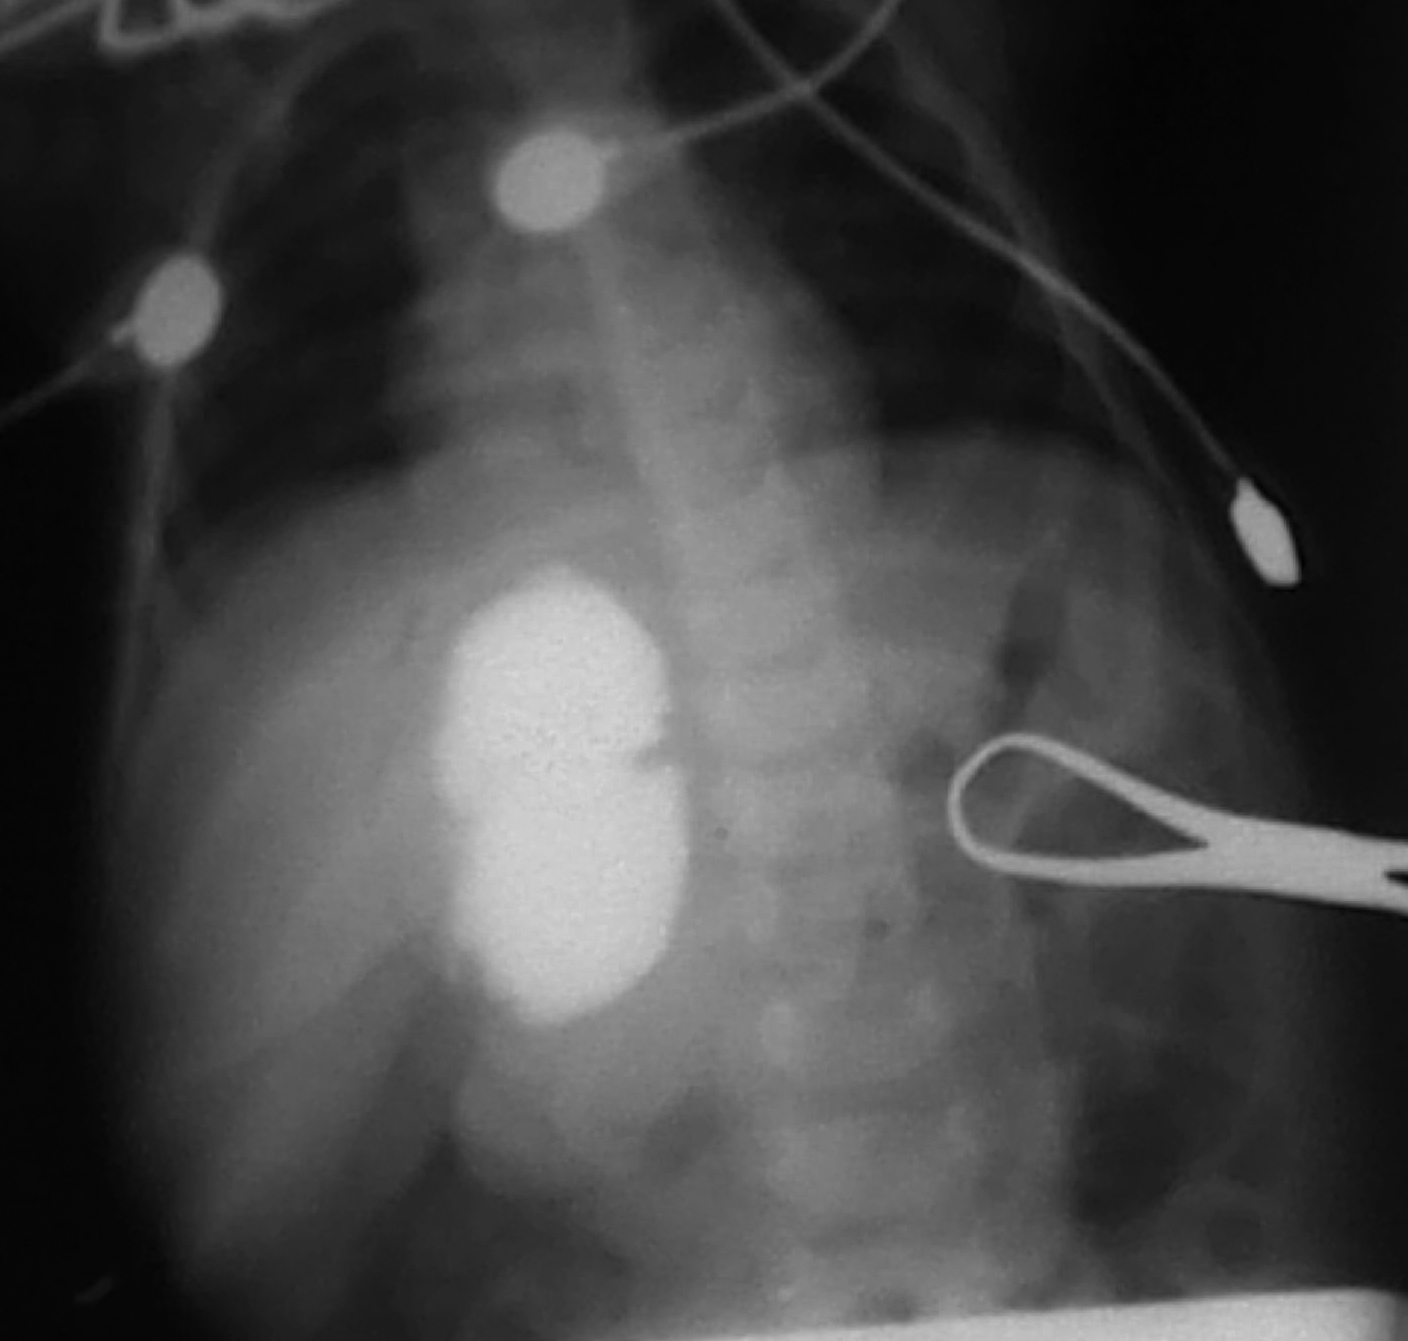

At operation, a cyst medial to the gall bladder, pushing the stomach and the pancreas anteriorly and intimately related to the second part of the duodenum was found (Fig. 2).The content of the cyst was clear mucous on aspiration. Intra-operative cystogram was performed that ruled out its communication with biliary and alimentary tracts (Fig. 3). The wall of the cyst was opened and stripping of mucosal lining performed after excising resectable portion of the cyst. The cyst was sharing common wall with duodenum and was non - communicating. The child made an uneventful recovery and was discharged on the fifth postoperative day. Histopathology of the specimen showed gastric mucosal lined tissue having smooth muscles in the wall along with ectopic pancreatic tissue (Fig. 4,5).

Figure 4: Microphotograph showing gastric mucosa with underlying muscle layer (x200).